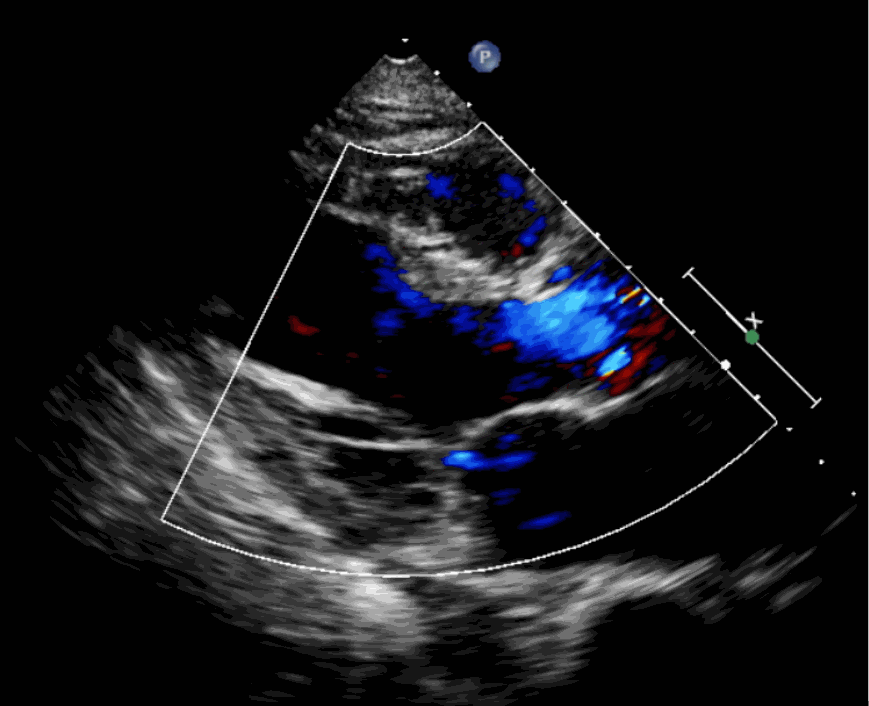

該例患者為62歲,女性,因“間歇性心悸、胸悶、氣短、胸痛1年,加重1周”之主訴入院。入院診斷:主動脈瓣重度關(guān)閉不全,二尖瓣、三尖瓣輕度關(guān)閉不全,心功能III級;冠狀動脈粥樣硬化性心臟病。行心臟超聲心動圖提示“主動脈瓣重度關(guān)閉不全;瓣口水平以下左室下壁、后下壁搏幅減低;EF值 0.30,左房、左室大、右房大小正常高限;二尖瓣、三尖瓣關(guān)閉不全;輕度肺動脈高壓(收縮壓42mmHg);主動脈硬化;左室收縮功能重度減低。經(jīng)心血管外科劉洋、楊劍教授、麻醉科陳敏教授及超聲科孟欣教授等專家團(tuán)隊綜合評估,判定患者為外科手術(shù)高危患者。

術(shù)前超聲影像圖